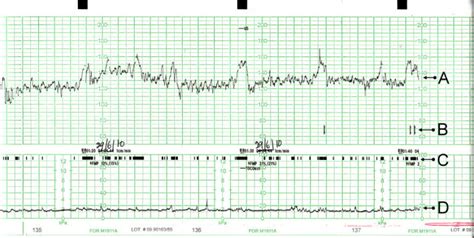

Was bedeuten die Kurven auf dem CTG?

Fetale Herzfrequenz (FHF)

Eine gesunde fetale Herzfrequenz liegt in der Regel zwischen 110 und 160 bpm. Die FHF-Kurve kann verschiedene Muster zeigen, darunter Akzelerationen (vorübergehende Erhöhungen der FHF) und Dezelerationen (vorübergehende Abnahmen der FHF), die auf die Reaktion des Fötus auf Wehen oder mögliche Stressfaktoren hinweisen. Die Variabilität/Oszillation dieser Kurve, also die Fluktuation der Herzfrequenz um einen Mittelwert, liefert wichtige Hinweise auf den Zustand des autonomen Nervensystems des Fötus.

Wehentätigkeit

Die untere Kurve gibt Aufschluss über die Häufigkeit, Dauer und Stärke der Wehen. Regelmäßige, starke Kontraktionen sind ein Zeichen für den Fortschritt der Geburt. Nicht jede Kontraktion ist eine Geburtswehe; oft bemerkt man die im CTG aufgezeichneten Kontraktionen gar nicht.